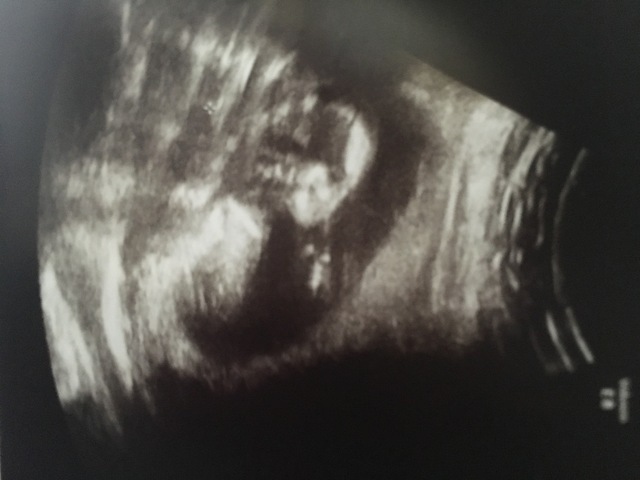

15週3日(15w3d・男の子)|キキくん さん(30歳)

エコー写真撮影時のエピソード:

これまでのエコー写真は赤ちゃんの姿がとても分かりづらかったけど、この日初めてはっきりとした姿を見せてくれました!一番喜んでくれたのは、やっぱり主人!「おぉ~わかる!わかる!これが頭で、これが腕で、これが足でしょ!」と、とても興奮して話してくれました!男の人はなかなか自分がパパになる実感がないといいますが、この時は本当に嬉しそうでした。両親や外国人の友達にも写真を写メして送ったら、とても喜んでくれました!赤ちゃんの存在って本当にすごいなと感じました!!